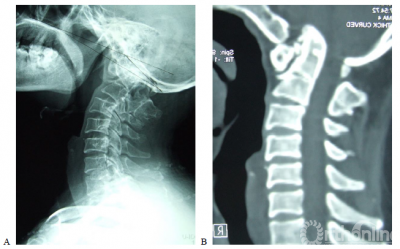

图1. 女,50岁,合并颈2/3分节不全,类风湿关节炎病史13年。A,术前X片示齿突向头侧移位,突入枕骨大孔内;B,术前CT示寰枢关节间异常骨性连接,齿突向上移位,超过McRae线7.02mm;C,术前T2加权MRI示上颈髓受压,CMA为109度; D,E术后X片及CT示齿突复位,低于McRae线9.89mm;F,G术后3年CT及三维重建示齿突复位得到维持,枕颈牢固融合;H,术后3年T1加权MRI示上颈髓受压解除,CMA改善到到155度。